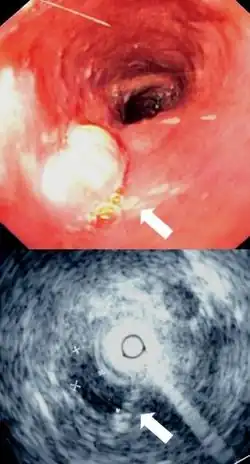

Although an occlusive tumor may be suspected on a barium swallow or barium meal, the diagnosis is best made with an examination using an endoscope. This involves the passing of a flexible tube with a light and camera down the esophagus and examining the wall, and is called an esophagogastroduodenoscopy. Biopsies taken of suspicious lesions are then examined histologically for signs of malignancy.

Additional testing is needed to assess how much the cancer has spread (see § Staging, below). Computed tomography (CT) of the chest, abdomen and pelvis can evaluate whether the cancer has spread to adjacent tissues or distant organs (especially liver and lymph nodes). The sensitivity of a CT scan is limited by its ability to detect masses (e.g. enlarged lymph nodes or involved organs) generally larger than 1 cm.[44][45] Positron emission tomography is also used to estimate the extent of the disease and is regarded as more precise than CT alone.[46] PET/MR as a novel modality has shown promising results in preoperative staging with fair feasibility and good correlation in comparison to PET/CT. It can enhance tissue differentiation with lowering the radiation dose to the patient.[47] Esophageal endoscopic ultrasound can provide staging information regarding the level of tumor invasion, and possible spread to regional lymph nodes.

Endoscopic image of Barrett esophagus – a frequent precursor of esophageal adenocarcinoma

Endoscopy and radial endoscopic ultrasound images of a submucosal tumor in the central portion of the esophagus- Contrast CT scan showing an esophageal tumor (axial view)